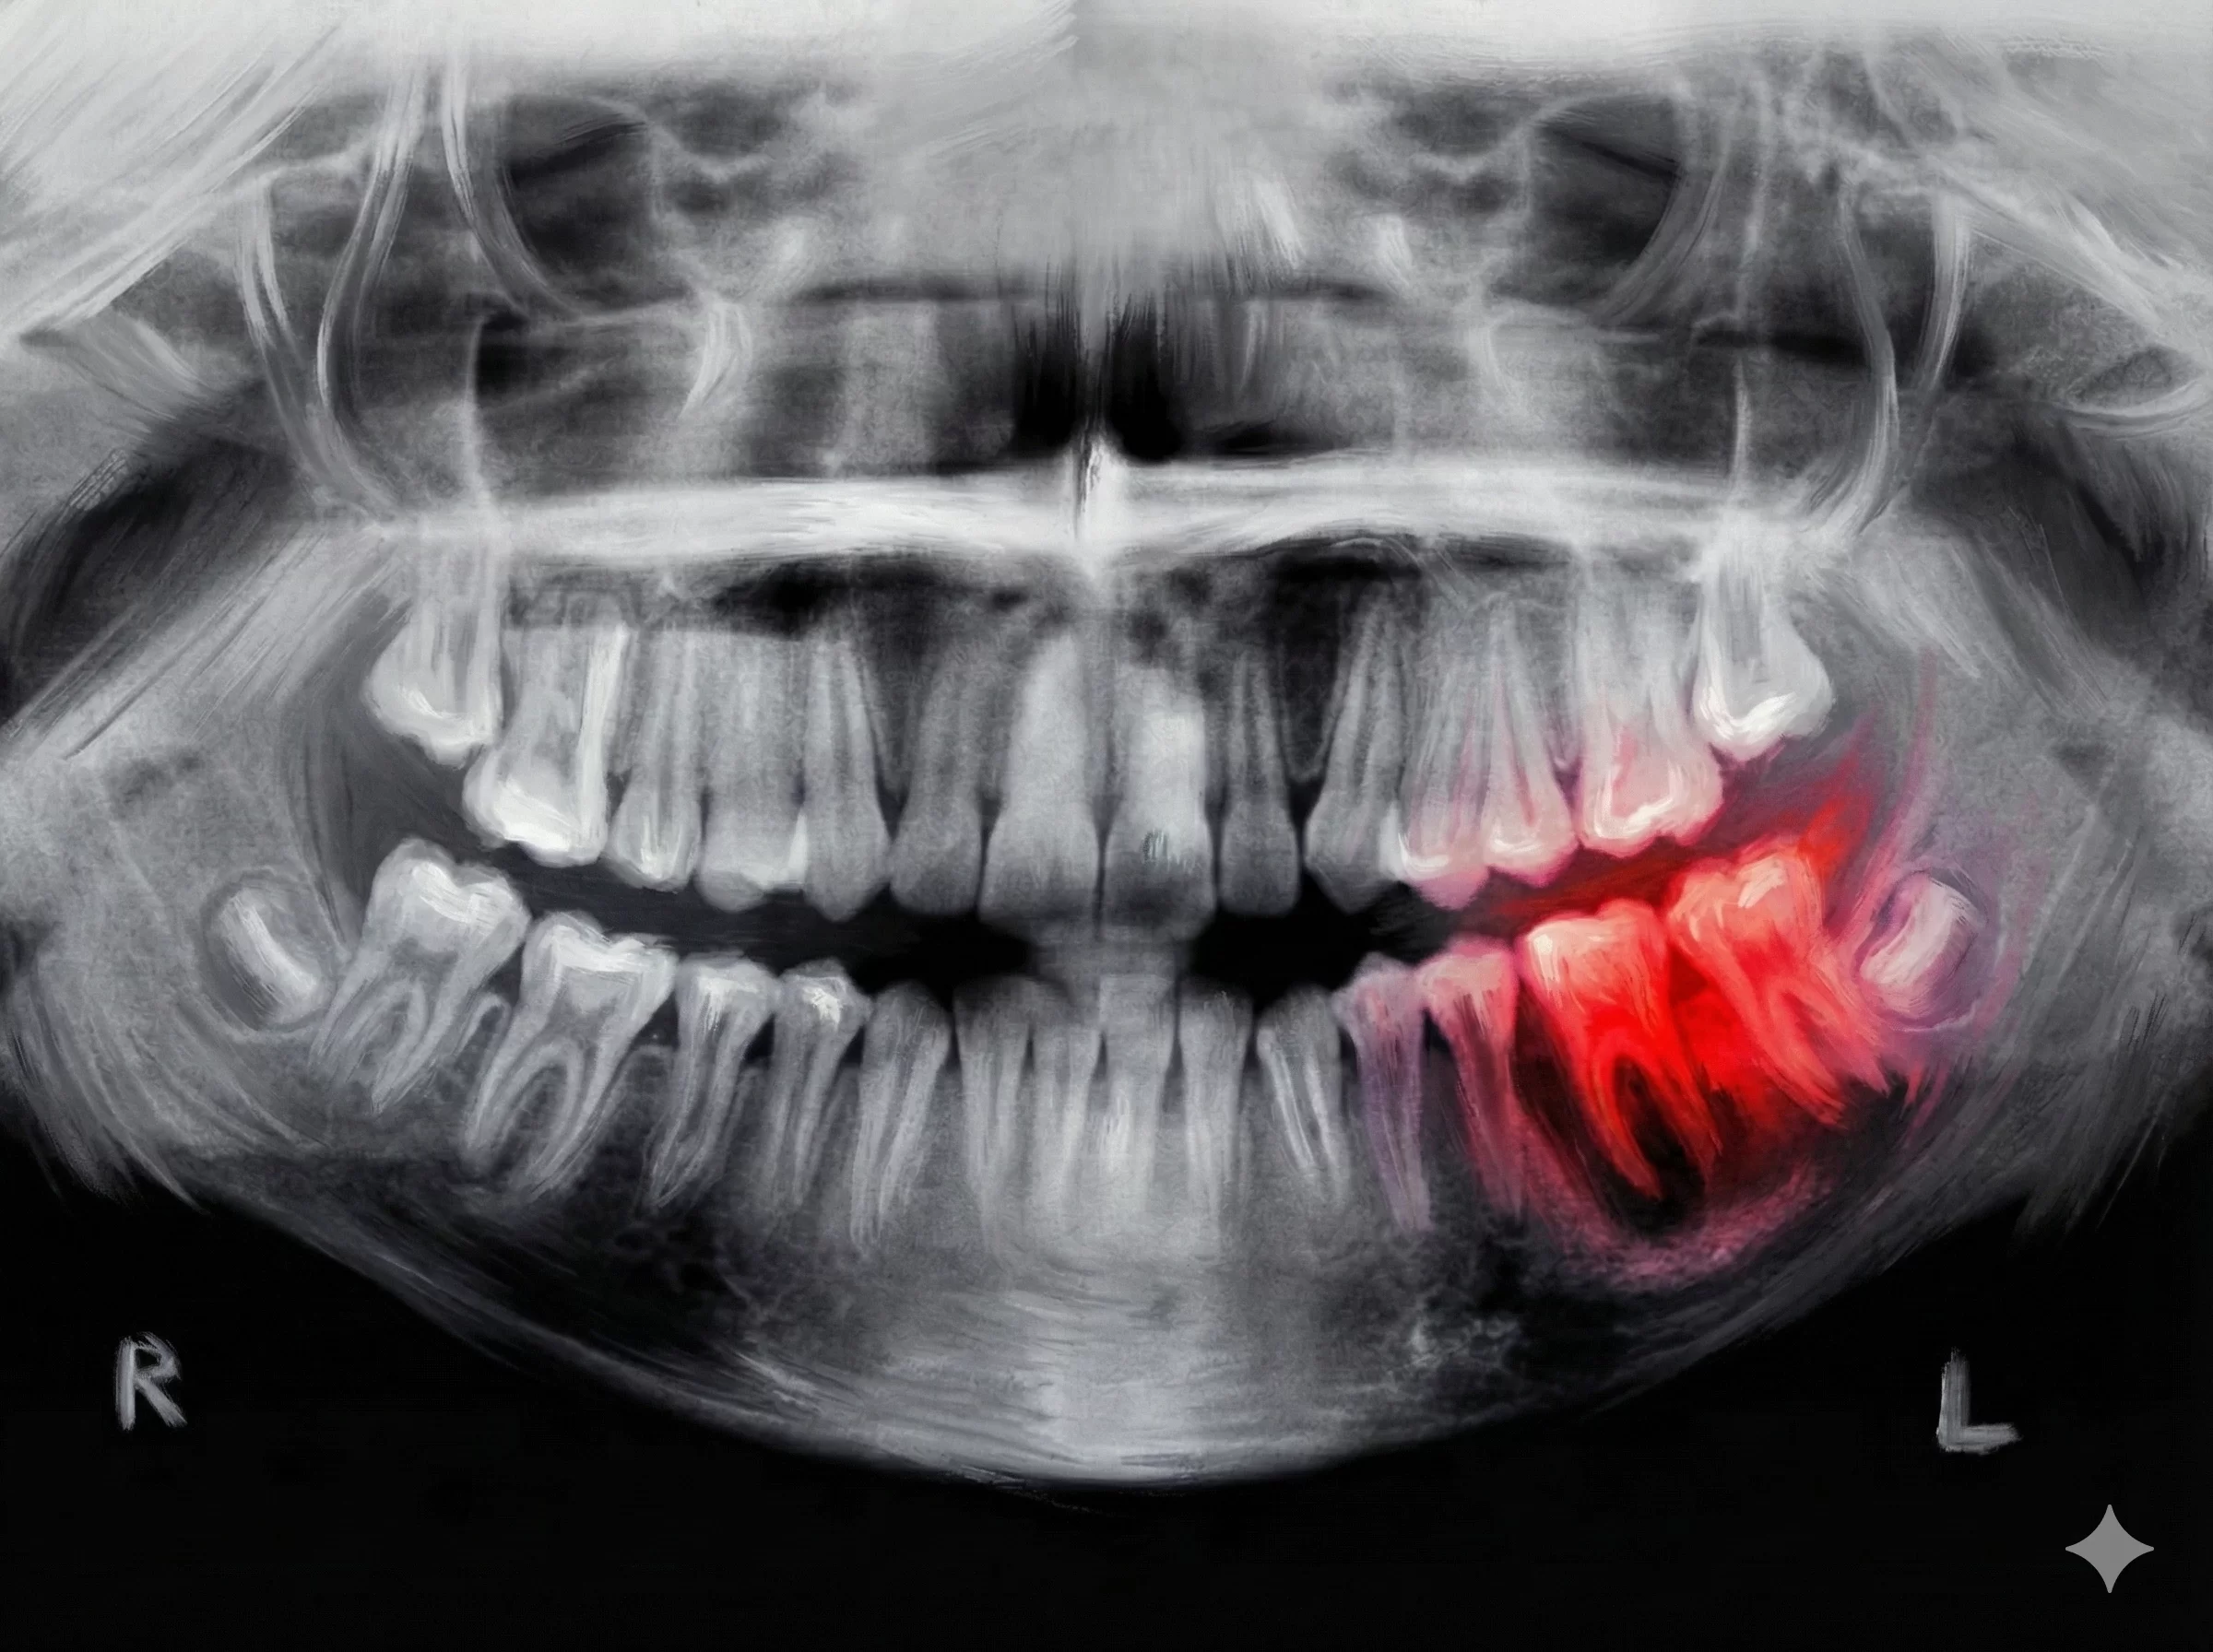

Hayvanlar üzerindeki başarılı sonuçların ardından başlayan insan deneyleri, yaklaşık 11 ay sürecek titiz bir takvime sahip. İlk aşamada, en az bir dişi eksik olan 30 ila 64 yaş arasındaki 30 erkek gönüllü üzerinde ilacın etkinliği ve güvenliği test ediliyor. İlaç, hastalara intravenöz (damar yoluyla) olarak veriliyor. Daha önceki hayvan deneylerinde hiçbir yan etki rapor edilmemiş olması, insan deneyleri için de büyük bir iyimserlik yaratıyor.

| Aşama 1 (Eylül 2024) | 30-64 yaş arası 30 yetişkin erkek | Güvenlik ve temel etkinlik testi |

| Aşama 2 (Gelecek Adım) | 2-7 yaş arası çocuklar (4+ diş eksikliği olan) | Doğuştan gelen eksikliklerde etkinlik |

| Aşama 3 (Hedef 2030) | Tüm dişsizlik vakaları (Yaralanma, çürüme vb.) | Genel kullanıma sunulması |